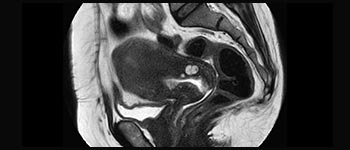

La Sra. Silvia Schiffer, directora y radióloga experta en la clínica Radiologie Schiffer, en Alemania, comparte sus experiencias con el sistema de RM Prodiva 1.5T.

Conozca cómo Ingenia Prodiva puede satisfacer sus necesidades clínicas.

Conozca la opinión de los primeros usuarios de Ingenia Prodiva 1.5T acerca de sus experiencias con el sistema y cómo influye este en su centro de diagnóstico por imagen.